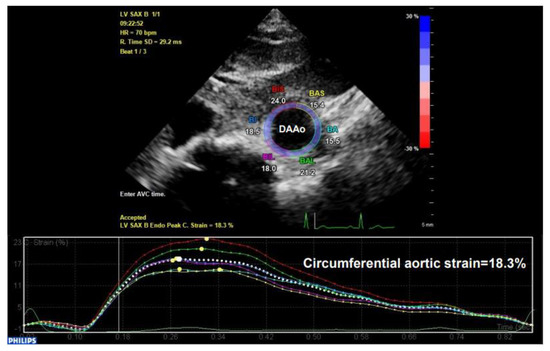

STI is another newly developed ultrasonographic method used to quantify the tissue wall’s deformation of subsurface structures with high spatial resolution. The speckle pattern can be tracked consecutively from frame to frame and ultimately resolved into angle-independent 2D and three-dimensional (3D) strain-based sequences, providing both quantitative and qualitative information regarding tissue deformation and motion. So far, speckle tracking using in-vessel deformation has been limited to 2D-STI, while the application of 3D-STI in vessels is still undergoing technological developments. 2D-STI can be obtained by B-mode, and the corresponding circumferential strain rate can be calculated by using the dedicated software. Based on frame-by-frame tracking of tiny echo-dense speckles within the tissue, 2D-STI enables the calculations of motion and deformation variables, such as velocity, displacement, strain, and strain rate, through the assessment of the tissues’ lengthening and shortening [43,61]. As illustrated in the upper panel of Figure 9, with a 2D ultrasonographic image of the human aorta, a line was manually drawn along the inner side of the DAAo circumference, and the additional lines within a 15-mm-wide region of interest would be automatically generated by the software (Automated Cardiac Motion Quantificationᴬ⋅ᴵ, Qlab 13.0; Philips Healthcare, Amsterdam, The Netherlands). The shape and width of the regions of interest could be manually adjusted. A cine loop preview feature allowed visual confirmation that the internal line followed the vascular expansion and recoil movements throughout the cardiac cycle. Based on these measurements, the circumferential strain rate can be automatically or semi-automatically calculated by the software, as shown in the lower panel of Figure 9.

Figure 9. The illustration of human aortic assessments by two-dimensional (2D) speckle tracking. Intraoperative 2D speckle tracking analysis from a short-axis view of descending abdominal aorta (DAAo) in a healthy individual. The circumferential strain profile is displayed on a positively directed curve with a peak value of 18.3%.